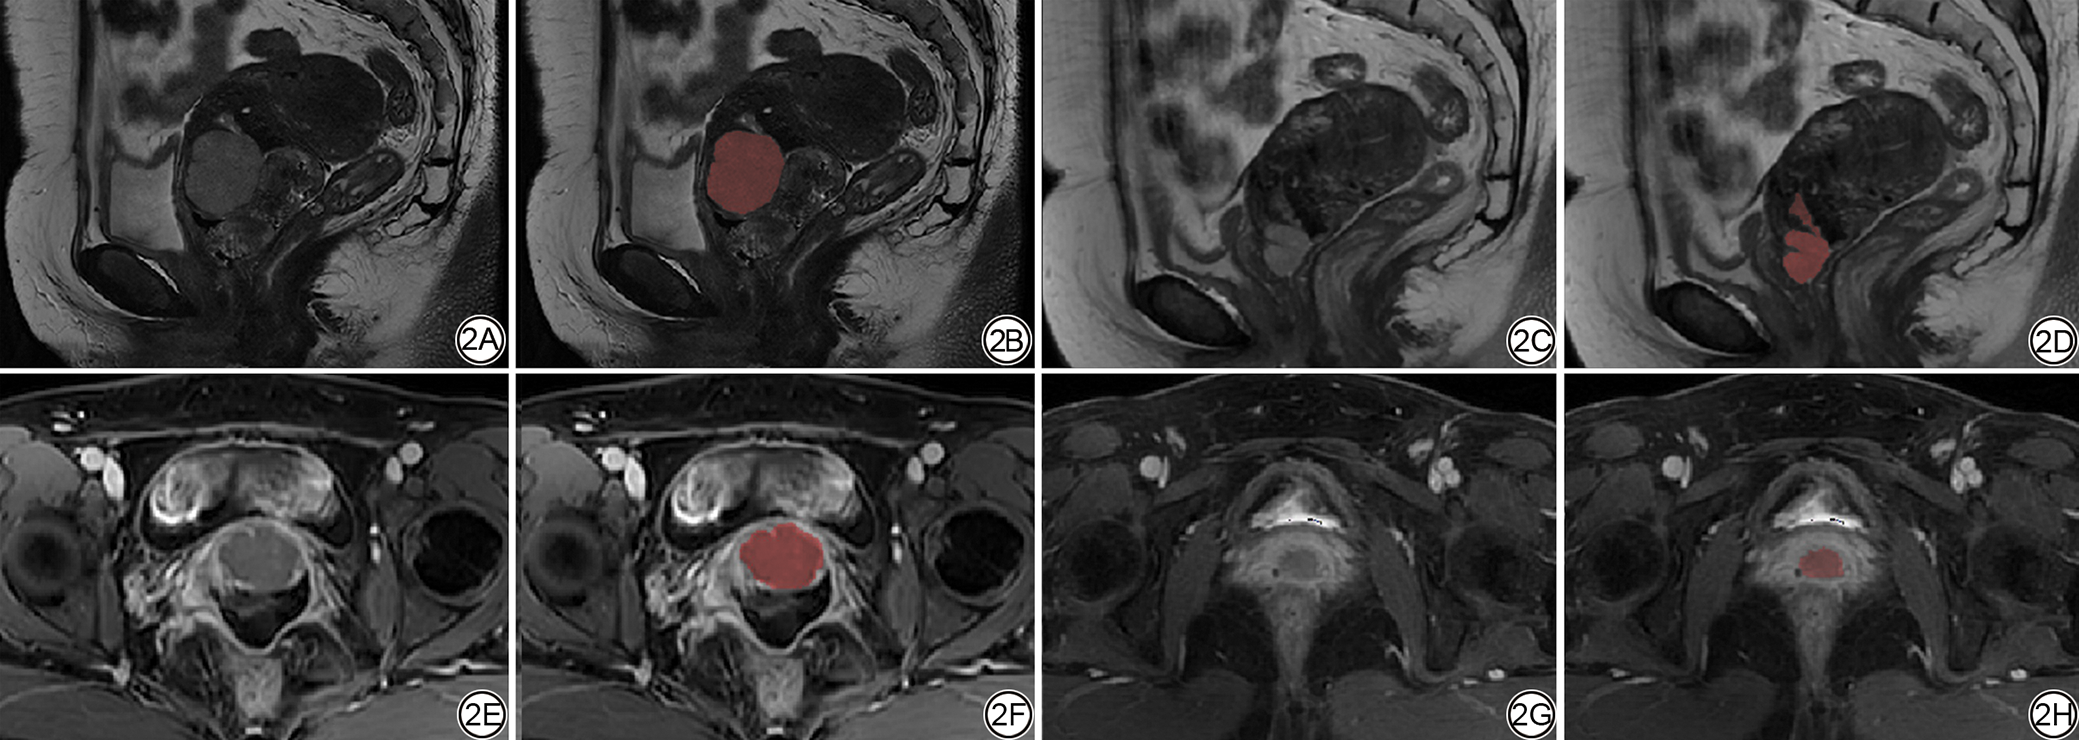

将格式转换后将图像导入ITK-SNAP3.8(版本4.2.0,http://www.itksnap.org)软件,由一位具有3年经验的放射科住院医师参考所有序列图像,在Sag_T2WI和Ax_T1CE序列上沿肿瘤轮廓在所有连续层面上逐层勾画感兴趣区(region of interest, ROI)(图2图3),然后由具有二十多年经验的放射科主任医师进行审查,对有争议的ROI进行协商并达成一致。

图2  女,47岁,中/高风险组。2A、2B:NACT前Sag_T2WI序列图像;2C、2D:NACT后Sag_T2WI序列图像;2E、2F:NACT前Ax_T1CE序列图像;2G、2H:NACT后Ax_T1CE序列图像。NACT:新辅助化疗;Sag_T2WI:矢状位T2加权成像;Ax_T1CE:轴位对比增强T1加权成像。

Fig. 2  Female, 47 years old, intermediate-to-high-risk group. 2A, 2B: Sag_T2WI images before NACT; 2C, 2D: Sag_T2WI images after NACT; 2E, 2F: Ax_T1CE images before NACT; 2G, 2H: Ax_T1CE images after NACT. NACT: neoadjuvant chemotherapy; Sag_T2WI: sagittal T2-weighted imaging; Ax_T1CE: axial contrast-enhanced T1-weighted imaging.